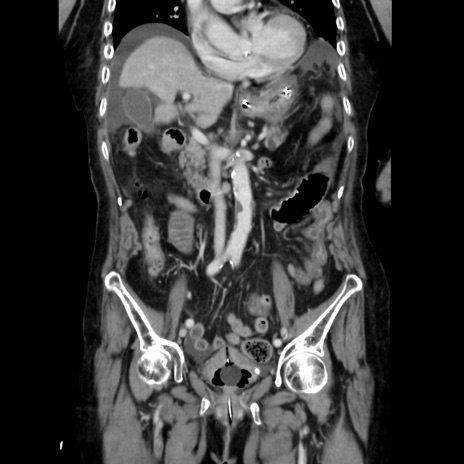

症例40(冠状断像)

【症例】90歳代女性

【主訴】腹痛・嘔吐

【現病歴】 食欲低下、嘔吐があり昨日他院受診。肺炎と診断され入院となる。入院後より腹部全体に圧痛あり。胃管留置され経過みていたが、症状持続するため、

当院転院となる。

【既往歴】胸椎圧迫骨折、胆石症

【身体所見】腹部:中央に激痛あり、圧痛あり、反跳痛不明

【データ】WBC 17100、CRP 18.82

冠状断像